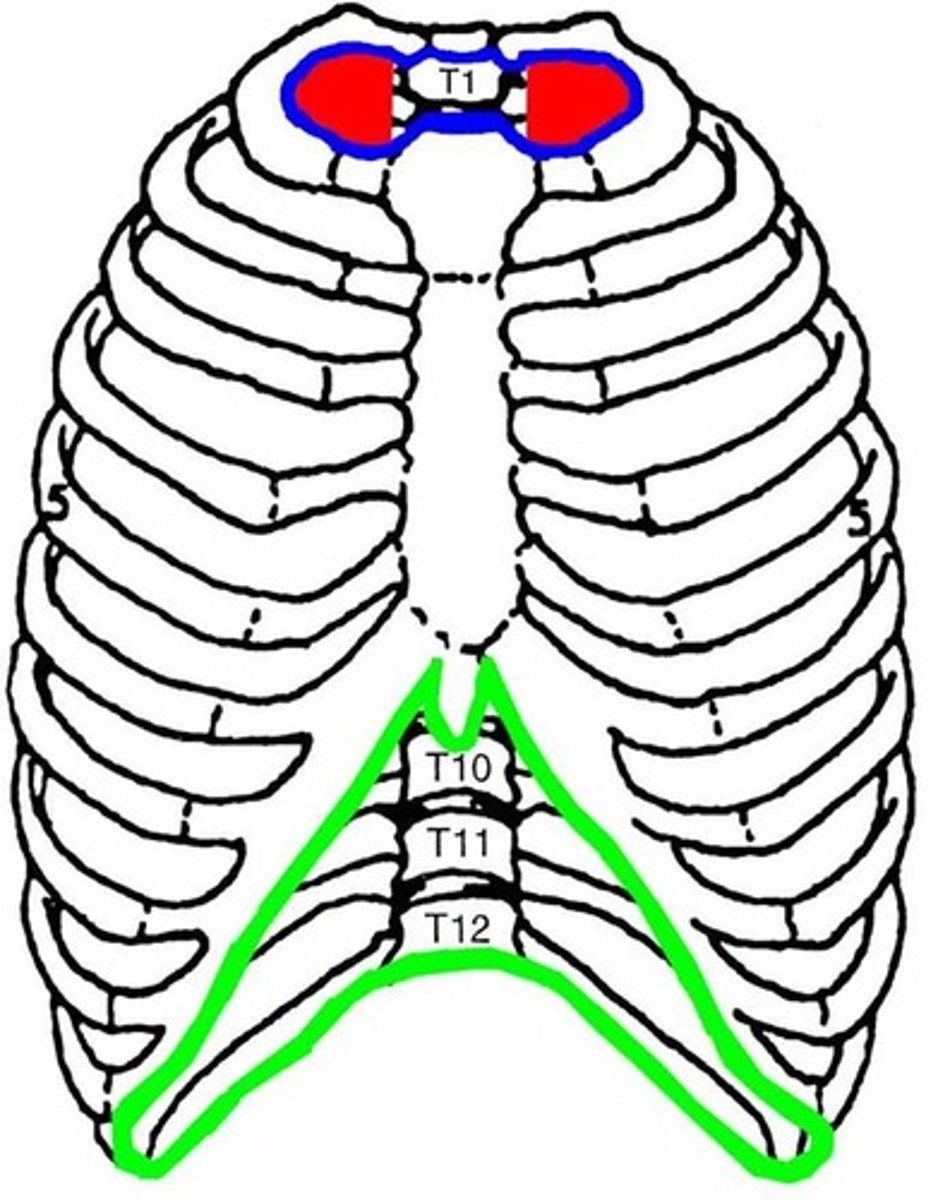

Which are the true ribs and what makes them "true" ?

1-7, attach directly to sternum via costal cartilage

Which are false ribs? Why?

ribs 8, 9, 10 (usually), attach directly to sternum but by the cartilage of the superior rib

Which are the "floating ribs" and why?

11-12, Don't attach in any way to sternum

Xiphoid process of sternum

(T10)

Midline marker for superior level of liver, central tendon of diaphram

inferior border border of heart

cartilaginous in young people. Bone after 40.

What is the suprasternal notch level to?

T2-T3

What is the sternal angle (manubriosternal joint) level to?

T4-T5

What is the xiphisternal joint level to?

T9